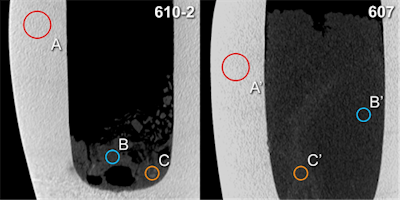

Hounsfield unit (HU) measurements: Analogous placement of regions of interest A and A' (calcite mineral), B and B' (surrounding material), C and C' (radiopaque structures) for two canopic jars (inventory numbers 610-2 and 607, respectively) on sagittal multiplanar CT scan reconstructions (slab thickness 1.5 mm). All images courtesy of Dr. Patrick Eppenberger.The researchers performed the study as part of a larger transdisciplinary mummy research project linking medicine, evolutionary biology, and Egyptology. They performed basic noninvasive radiological procedures before further invasive procedures, such as sampling for histological, chemical, or genetic analysis. Radiology also helps museums' curators decide whether to open the jars or keep them untouched.

CT reconstructions (top) and correlative maximum intensity projections of MRI scans (bottom) of the three canopic jars with solid contents. Black arrows (CT) and white arrows (MRI) indicate corresponding structures of organ fragment like morphology, probably intestine.The thickness and high density of the calcite mineral of the canopic jars limited x-ray image contrast. CT scans showed few artifacts and revealed hyperdense structures of organ-specific morphology, surrounded by a hypodense homogeneous material. CT scans revealed all the jars were partially filled with material of mostly heterogeneous density (mean 208 Hounsfield units [HU]).

In one jar (jar 607), structures of distinct longitudinal morphology and higher density (mean 344 HU, range from 71 HU to 595 HU) were clearly distinguishable from a homogeneous surrounding material of lower density (mean 186 HU, range from -88 HU to 448 HU).

"Although x-ray imaging often remains the most practical imaging modality for many paleoradiological applications (since it can be performed on site, for example at a museum or in the field, using portable equipment), for the purpose of this study it was but of limited value," the authors wrote. "The poor image quality can be explained as a result of the substantial thickness and rather high density of the calcite mineral composing the examined canopic jars (mean 2,215 HU), compared with the literature results for other minerals and nonmetallic materials."